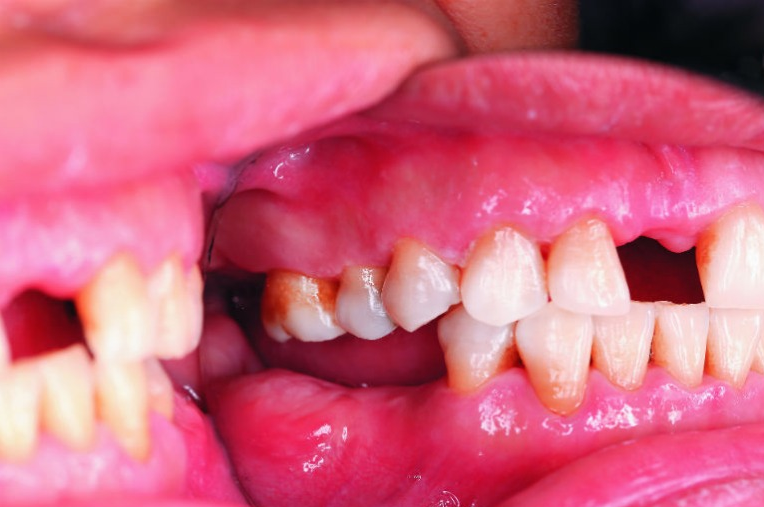

經過牙周治療,牙周組織恢復健康(圖片來源/新光醫院提供)